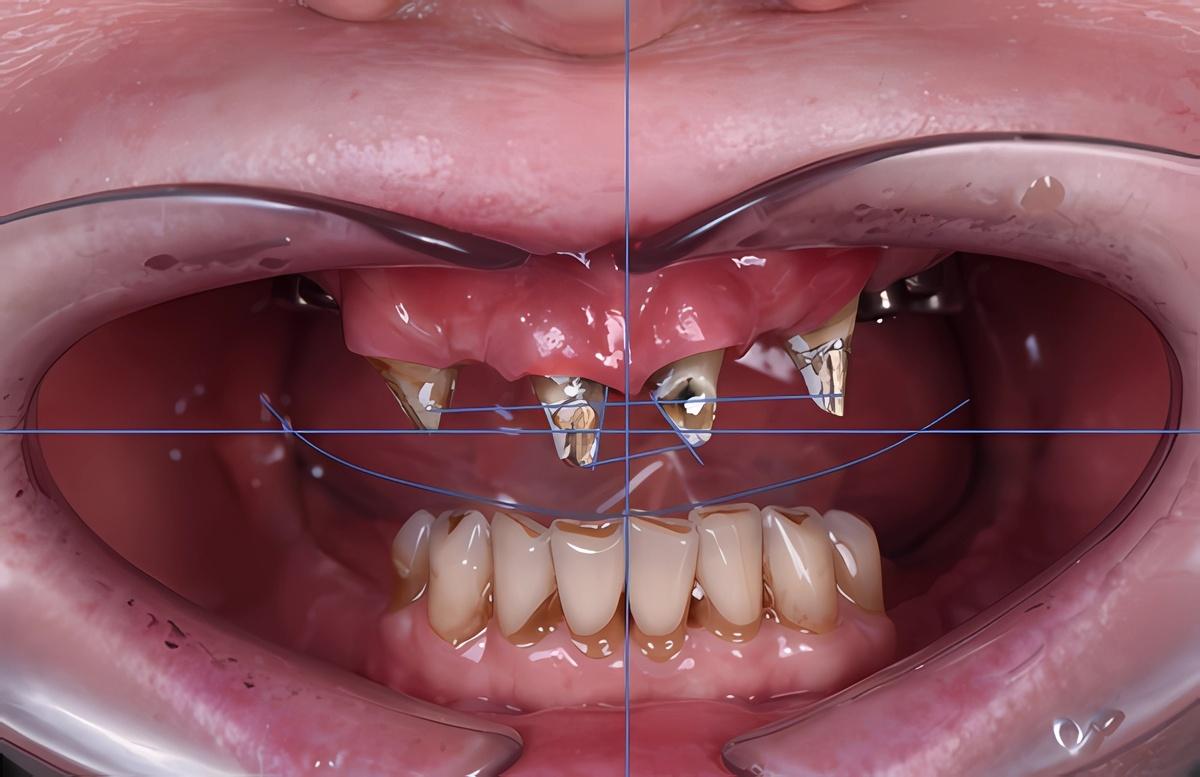

Верхний зубной ряд:

-

Справа. Протяженный мост на 5 единиц с опорой на 3 свои зуба

Передние зубы. Две одиночные коронки + мост на 3 единицы

Слева. 4 коронки с опорой на 4 импланта + зуб мудрости

Нижний зубной ряд:

Справа. Мост на 3 единицы с опорой на 2 импланта + дистопированный зуб мудрости

Передние зубы. 8 собственных +/- живых зубов

Слева. 1 свой зуб под коронкой, 2 коронки с опорой на 2 импланта + дистопированный зуб мудрости